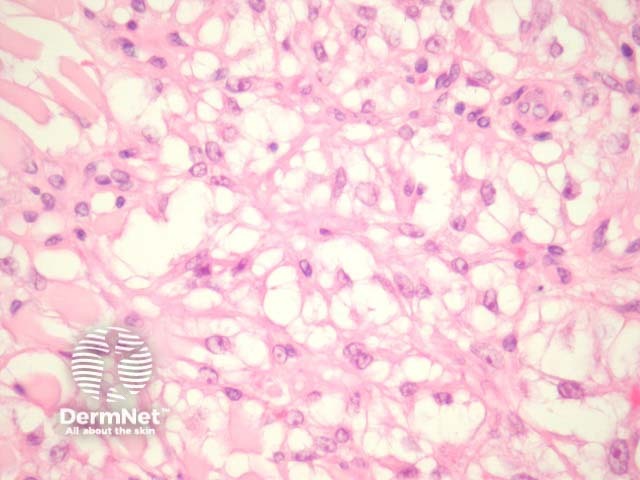

Sections show a discrete mass in the dermis (figure 1). The tumour is composed of epithelioid cells with clear to eosinophilic cytoplasm and round to oval nuclei with obvious nucleoli (figure 2-3). They frequently exhibit a nested or trabecular arrangement (figure 3).

Figure 2

Figure 3

Periodic acid-Shif (PAS) and PAS-Diastase stains showed glycogen deposition within the cytoplasm of the clear cells of PEComa.

Immunohistochemistry reveals HMB-45 is strongly positive in all cases. Microftalmia associated transcription factor (MiTF) and desmin may show some staining. S-100 is negative.